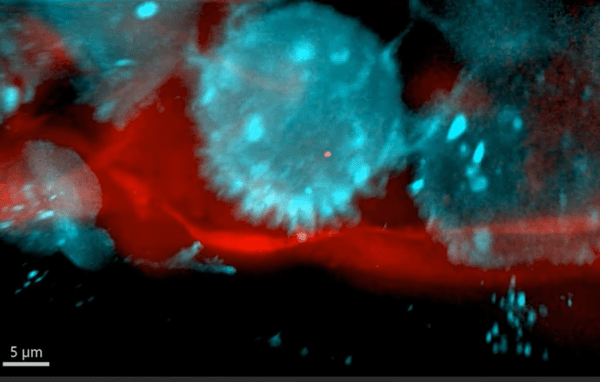

Parmi les éléments de l’environnement favorable aux cellules métastatiques figure le système immunitaire et notamment les macrophages qui sont impliqués dans une boucle paracrine avec les cellules tumorales au cours des stades métatastatiques initiaux. Le chimiotactisme des cellules métastatiques vers les vaisseaux sanguins se produit en réponse à des molécules telles que l’EGF sécrétés par les macrophages associés aux vaisseaux. Les cellules cancéreuses expriment le récepteur de l’EGF (EGFR) et sécrètent CSF-1, qui attire les macrophages et les incite à exprimer l’EGF, complétant ainsi une boucle de rétroaction paracrine positive. La signalisation entre le macrophage et la cellule tumorale affecte l’activité des régulateurs de l’actine tels que WASP et N-WASP, entraînant la formation de podosomes dans les macrophages et des invadopodes dans les cellules tumorales qui favorisent l’intravasation des cellules tumorales (Condeelis et Pollard, 2006).

La migration est souvent étudiée à partir de la tumeur primaire mais pour la formation des tumeurs secondaires, il ne faut pas oublier les étapes d’extravasation (sortie des vaisseaux sanguins vers le site de colonisation) et la migration à travers le nouveau tissu.

Signalons que des migrations collectives de cellules tumorales ont été observées. Dans ce cas, les cellules restent adhérentes entre elles. Au sein d’un amas tumoral en migration, une minorité de cellules se localisent en périphérie, dans le sens de la migration, et mènent le groupe. Ces cellules, appelées cellules leaders, présentent des forces de protrusion actives, interagissent avec la matrice extracellulaire (MEC) environnante et génèrent des forces de traction. Dans le cancer du sein, les cellules leaders sont définies histologiquement par l’expression de la kératine 14 (K14), une protéine des filaments intermédiaires (Cheung et al., 2016). Les fibroblastes associés au cancer (CAF) peuvent également être présents dans les amas tumoraux en migration et contribuer à l’invasion et à la migration collectives des tumeurs (Bayer et al., 2019).